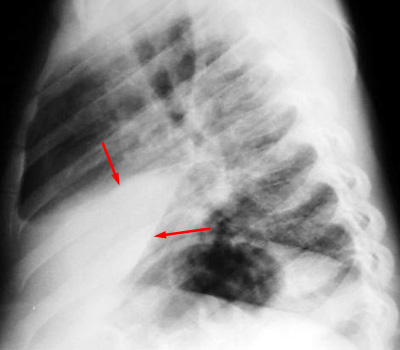

| Example of a right middle lobe pneumonia. PA and LAT CXR demonstrate consolidation in the right middle lobe. |